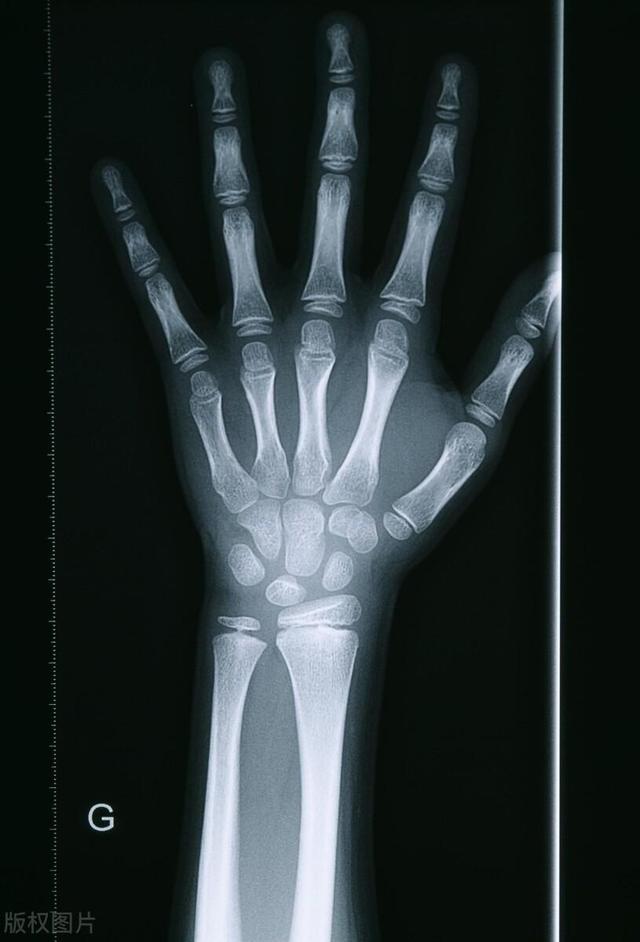

骨骺线是骨骺板的截面图像,在儿童拍摄的x光片上表现为一条透光带。简单来说,就是一个细条形状的黑影。

随着孩子的成长,骨骺线会不断硬化,最终变成骨头。在这期间,孩子的四肢不断的变化,帮助孩子长高。